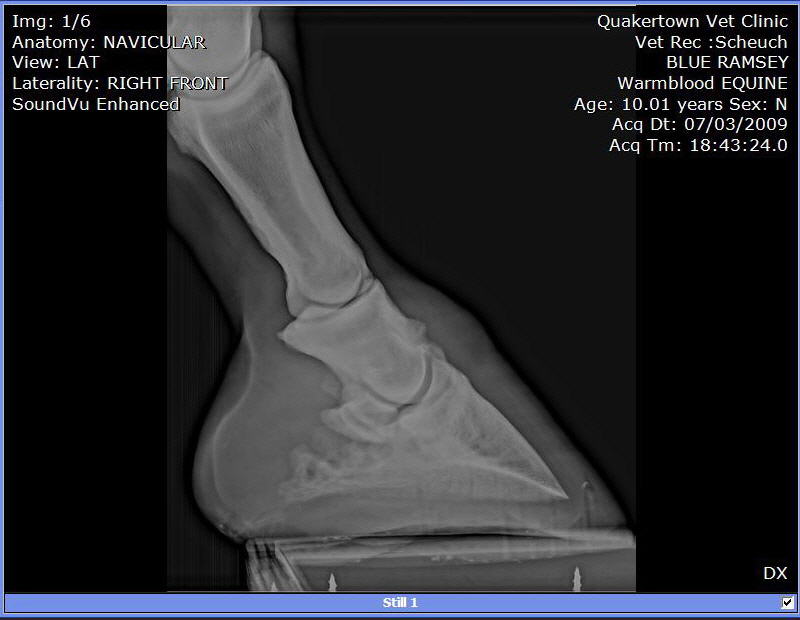

We put shoes on. Last week the farrier replaced them. He used a hoof tester checking of abscess or some reason for his slight limp. Since that day he as barely been able to walk. So, we called in the Vet to have him tested. A block in the heel helped him quite a bit. A block low in front and he was able to walk and trot without a limp.

X-rays:

I can see these are not images of a healthy hoof.

Among the many abnormalities the most important is the radiographs are clear for DJD of the coffin joint or what is often called low ringbone. No the hoof testers did not aggravate it, I suspect flexion of the joint during the exam did. You will find much information on this condition and what to expect at Diseases of Horses » Lameness » Diseases of the Lower Limb » Ringbone.

I can not read xrays to save my life, but I couldn't help feeling that this horse's foot was out of balance (from Image 3/6). I can't tell if its the way his foot is positioned on the plate, but he sure looks lopsided to me.

I would get his shoes off and get him back in balance ( to me he looks low on the outside and high on the inside. I'd be able to tell better if I could see the foot from the bottom to see which way the frog is leaning. I'd try to keep him as simple as possible at least for a few days to see how he handles being barefoot.

As rtrotter noted above the horse is either standing oddly or the foot is unbalanced from side to side in the above radiographs, careful management of balance and breakover could help this horse be as comfortable as possible.

Do the images suggest that the side bone has broken off?

No Guy it does not indicate it. Though we cannot say for sure this is a common appearance of a focal area of calcification for more on this see Diseases of Horses » Lameness » Diseases of the Hoof » Side Bone and the Collateral Cartilages.